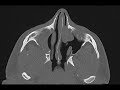

Uncinate Atelectasis

The first image was obtained four months prior to the remaining five images. It shows a clear right maxillary sinus, but opacification of the left maxillary sinus, widening of the left maxillary antrum, and opacification of the left nasal cavity by a mass which was found to be an inverted papilloma. On the subsequent CT following resection of this mass, the right maxillary sinus is completely opacified with concavity of the maxillary sinus wall, occlusion of the infundibulum, and lateralization of the uncinate. This is inward bowing is indicative of negative pressure and reflects uncinate atelectasis. This may result in enophthalmos and so-called silent sinus syndrome with possible diplopia. The differential diagnosis includes maxillary sinus hypoplasia.